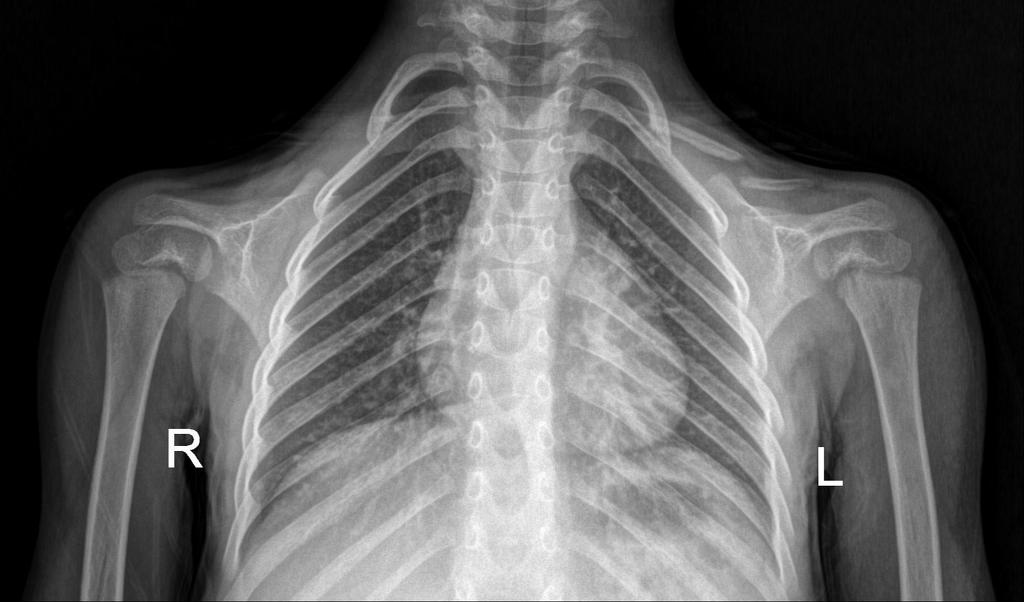

فحص الصدر

Chest x-ray

سلسلة تغريدات متكاملة عن الصدر وكل مايتعلق به خطوة خطوة و بالتفصيل:

ألقِ نظرة على تغريدة :